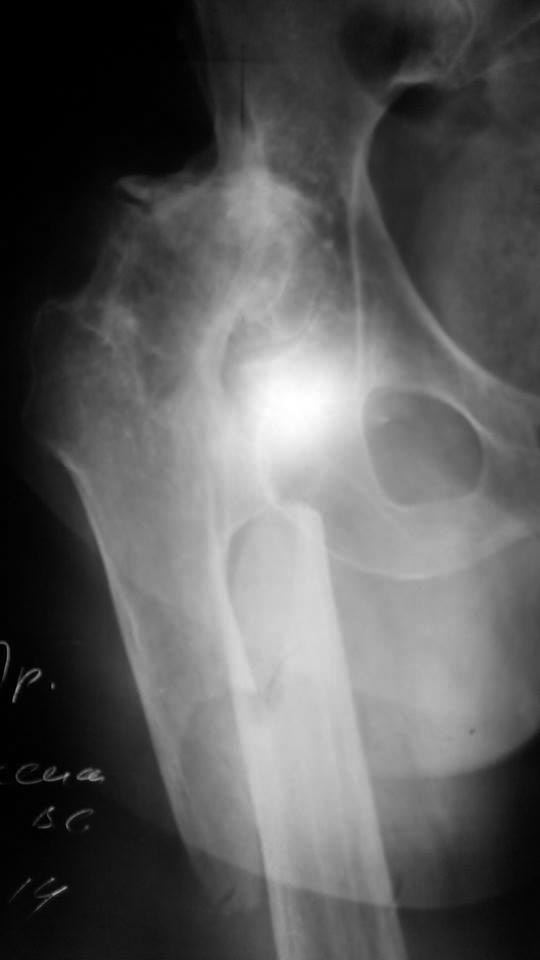

Бабульке 79 лет. Просьба предложить объём оперативного вмешательства.